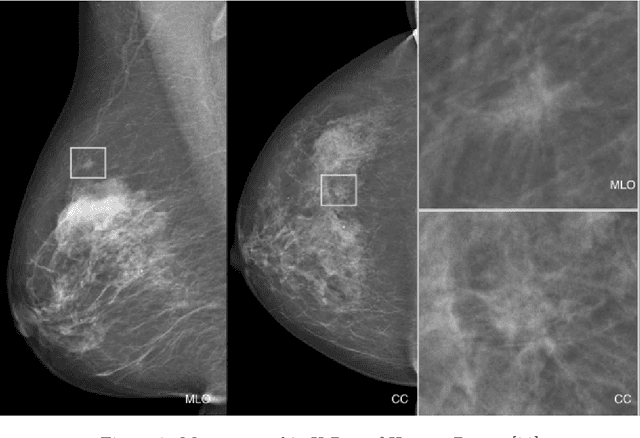

In the last decade, researchers working in the domain of computer vision and Artificial Intelligence (AI) have beefed up their efforts to come up with the automated framework that not only detects but also identifies stage of breast cancer. The reason for this surge in research activities in this direction are mainly due to advent of robust AI algorithms (deep learning), availability of hardware that can train those robust and complex AI algorithms and accessibility of large enough dataset required for training AI algorithms. Different imaging modalities that have been exploited by researchers to automate the task of breast cancer detection are mammograms, ultrasound, magnetic resonance imaging, histopathological images or any combination of them. This article analyzes these imaging modalities and presents their strengths, limitations and enlists resources from where their datasets can be accessed for research purpose. This article then summarizes AI and computer vision based state-of-the-art methods proposed in the last decade, to detect breast cancer using various imaging modalities. Generally, in this article we have focused on to review frameworks that have reported results using mammograms as it is most widely used breast imaging modality that serves as first test that medical practitioners usually prescribe for the detection of breast cancer. Second reason of focusing on mammogram imaging modalities is the availability of its labeled datasets. Datasets availability is one of the most important aspect for the development of AI based frameworks as such algorithms are data hungry and generally quality of dataset affects performance of AI based algorithms. In a nutshell, this research article will act as a primary resource for the research community working in the field of automated breast imaging analysis.